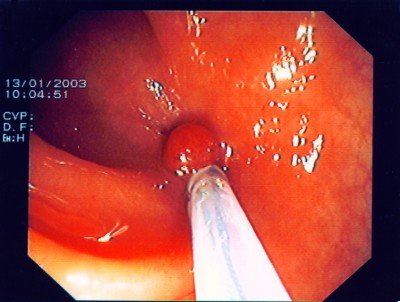

Großer Polyp des Dickdarmes